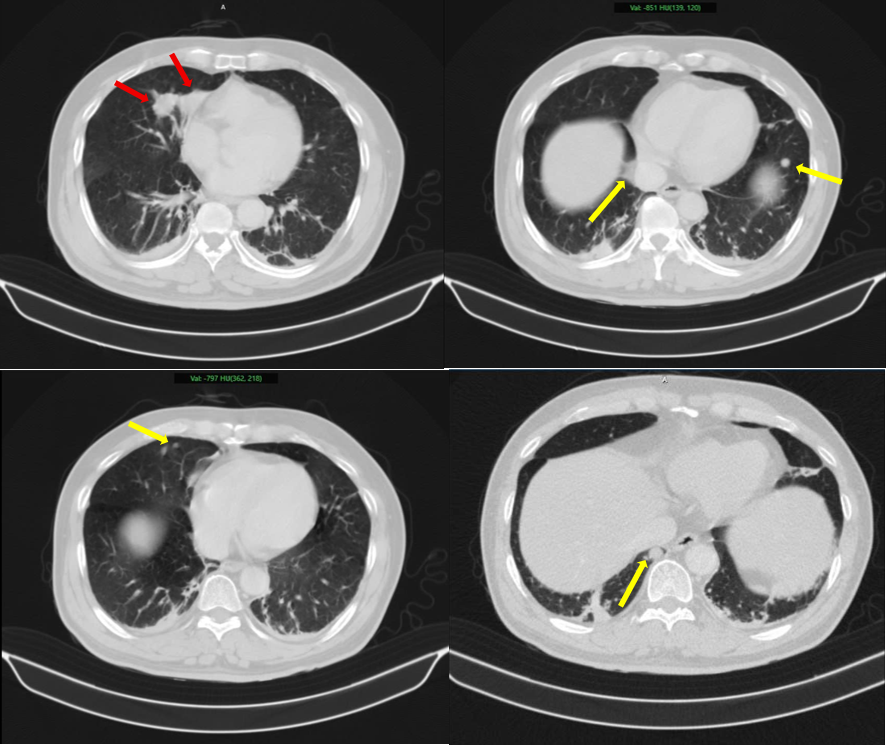

Tuy nhiên, qua thăm khám và thực hiện hàng loạt kỹ thuật cận lâm sàng hiện đại như chụp cắt lớp vi tính (CT), cộng hưởng từ (MRI), xạ hình xương và đặc biệt là PET/CT, các bác sĩ đã phát hiện nhiều tổn thương bất thường: khối u tại tuyến tiền liệt cùng các tổn thương ở phổi, tuyến thượng thận và xương.

Để làm rõ, các bác sĩ đã tiến hành sinh thiết, phân tích mô bệnh học kết hợp hóa mô miễn dịch. Kết quả cho thấy: Khối u phổi là ung thư biểu mô tuyến phổi; Khối u tuyến tiền liệt là ung thư biểu mô tuyến với điểm Gleason 9 – thuộc nhóm nguy cơ cao.

Điều quan trọng: hai loại ung thư này không liên quan di căn với nhau, mà là hai bệnh ung thư nguyên phát độc lập.